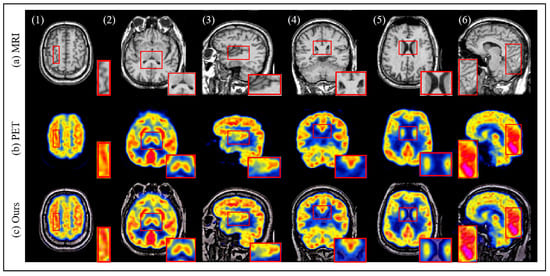

4.3. Results and Discussion